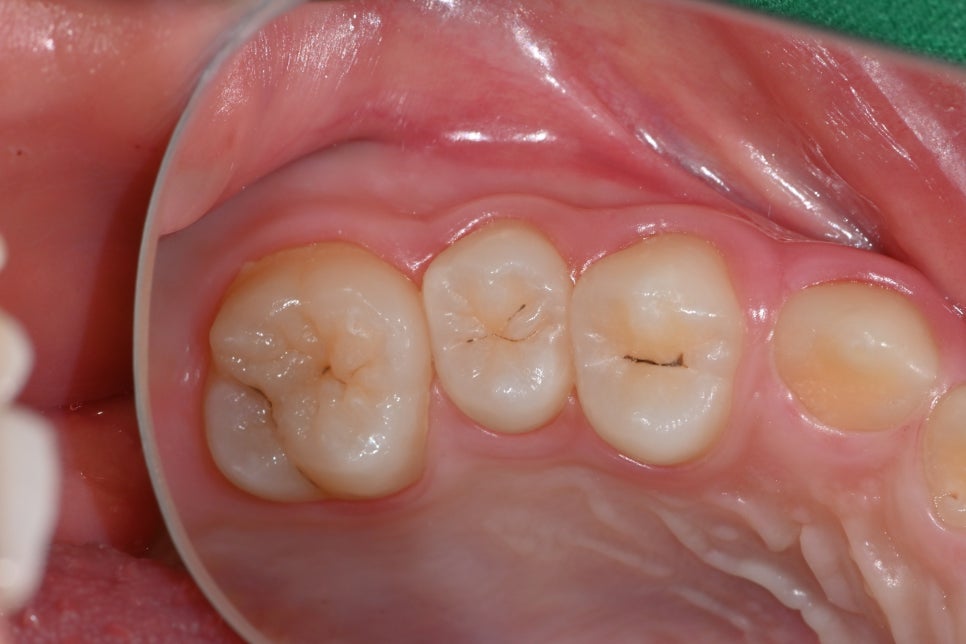

🦷 치료 전 사진 (03.14)

충치가 진행된 어금니의 초기 모습입니다.